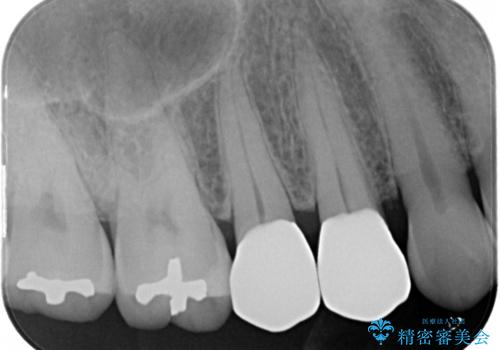

- 前歯のすきっぱを主訴にご来院された患者様です。他院でつめものやラミネートべニア(前歯の表面のみセラミックを貼り付ける)を行っていましたが、頻繁に外れることに悩まれており、クラウン(歯全体をセラミックがつつむ)をご希望されました。また、奥歯に大きな虫歯があり、歯が割れていたため、奥歯の治療も併せて行いました。

今回はまず欠けた場所を修復して見た目を回復させたのち、ラミネートべニアの仮歯をつくり、しばらく使用して考えて頂きました。メリットやデメリットを説明した結果、外れにくいセラミッククラウンをご選択頂きました。

咬み合わせや元のご自身の歯の色に特徴があったため、セラミッククラウンを修正したり、隣の歯を金属を外して白いつめものに変えたりして経過観察を長めに行いました。

右上の歯に関しても、大きな虫歯があったため、前歯の経過観察の間に治療を行いました。